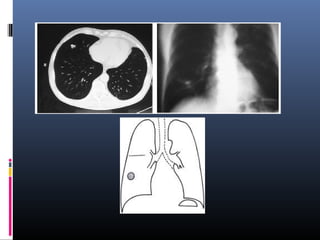

NODULO PULMONAR SOLITARIO

• Se describe com0 nódulo pulmonar solitario

NPS una lesión redondeada u oval, menor de

4 – 6 cm de diámetro .

• Puede variar su forma , ser calcificado,

cavitado .

NODULO PULMONAR

SOLITARIO